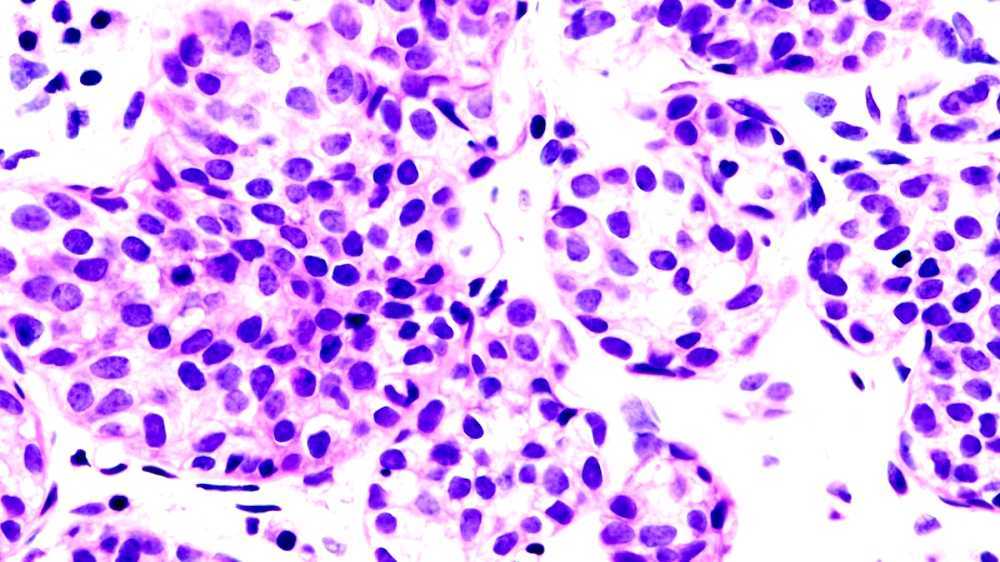

Diagnosis

Carcinomas can be definitively diagnosed through biopsy, including fine-needle aspiration (FNA), core biopsy, or subtotal removal of single node,. Microscopic examination by a pathologist is then necessary to identify molecular, cellular, or tissue architectural characteristics of epithelial cells.

Grading of carcinomas refers to the employment of criteria intended to semi-quantify the degree of cellular and tissue maturity seen in the transformed cells relative to the appearance of the normal parent epithelial tissue from which the carcinoma derives.

Grading of carcinoma is most often done after a treating physician and/or surgeon obtains a sample of suspected tumor tissue using surgical resection, needle or surgical biopsy, direct washing or brushing of tumor tissue, sputum cytopathology, etc. A pathologist then examines the tumor and its stroma, perhaps utilizing staining, immunohistochemistry, flow cytometry, or other methods. Finally, the pathologist classifies the tumor semi-quantitatively into one of three or four grades, including: